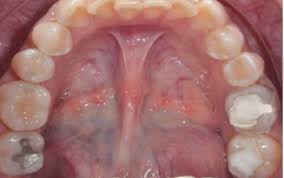

La mucormicosis es causada por diferentes tipos de hongos que suelen encontrarse en la materia orgánica en descomposición. Los síntomas del enfisema pulmonar pueden parecerse a los de otras condiciones de los pulmones o problemas médicos. § mucormicosis rinocerebral § mucormicosis pulmonar § mucormicosis gastrointestinal § mucormicosis cutánea § mucormicosis renal. Publicado por elsevier españa, s.l.u. These molds live throughout the environment.

Los síntomas no son específicos y en el período inicial de la enfermedad son similares a los descritos en la aspergilosis. Rx de trax lavado bronco alveolar biopsia. Nathalie quiroz1, janeth del pilar villanueva2, edgar andrés lozano3. Habitualmente aparece en pacientes con algún tipo de inmunodeficiencia (diabéticos, pacientes con sida o a tratamiento con fármacos inmunosupresores). Ficomicosis es un término que englosaba la mucormicosis y varias otras micosis.

Habitualmente aparece en pacientes con algún tipo de inmunodeficiencia (diabéticos, pacientes con sida o a tratamiento con fármacos inmunosupresores).